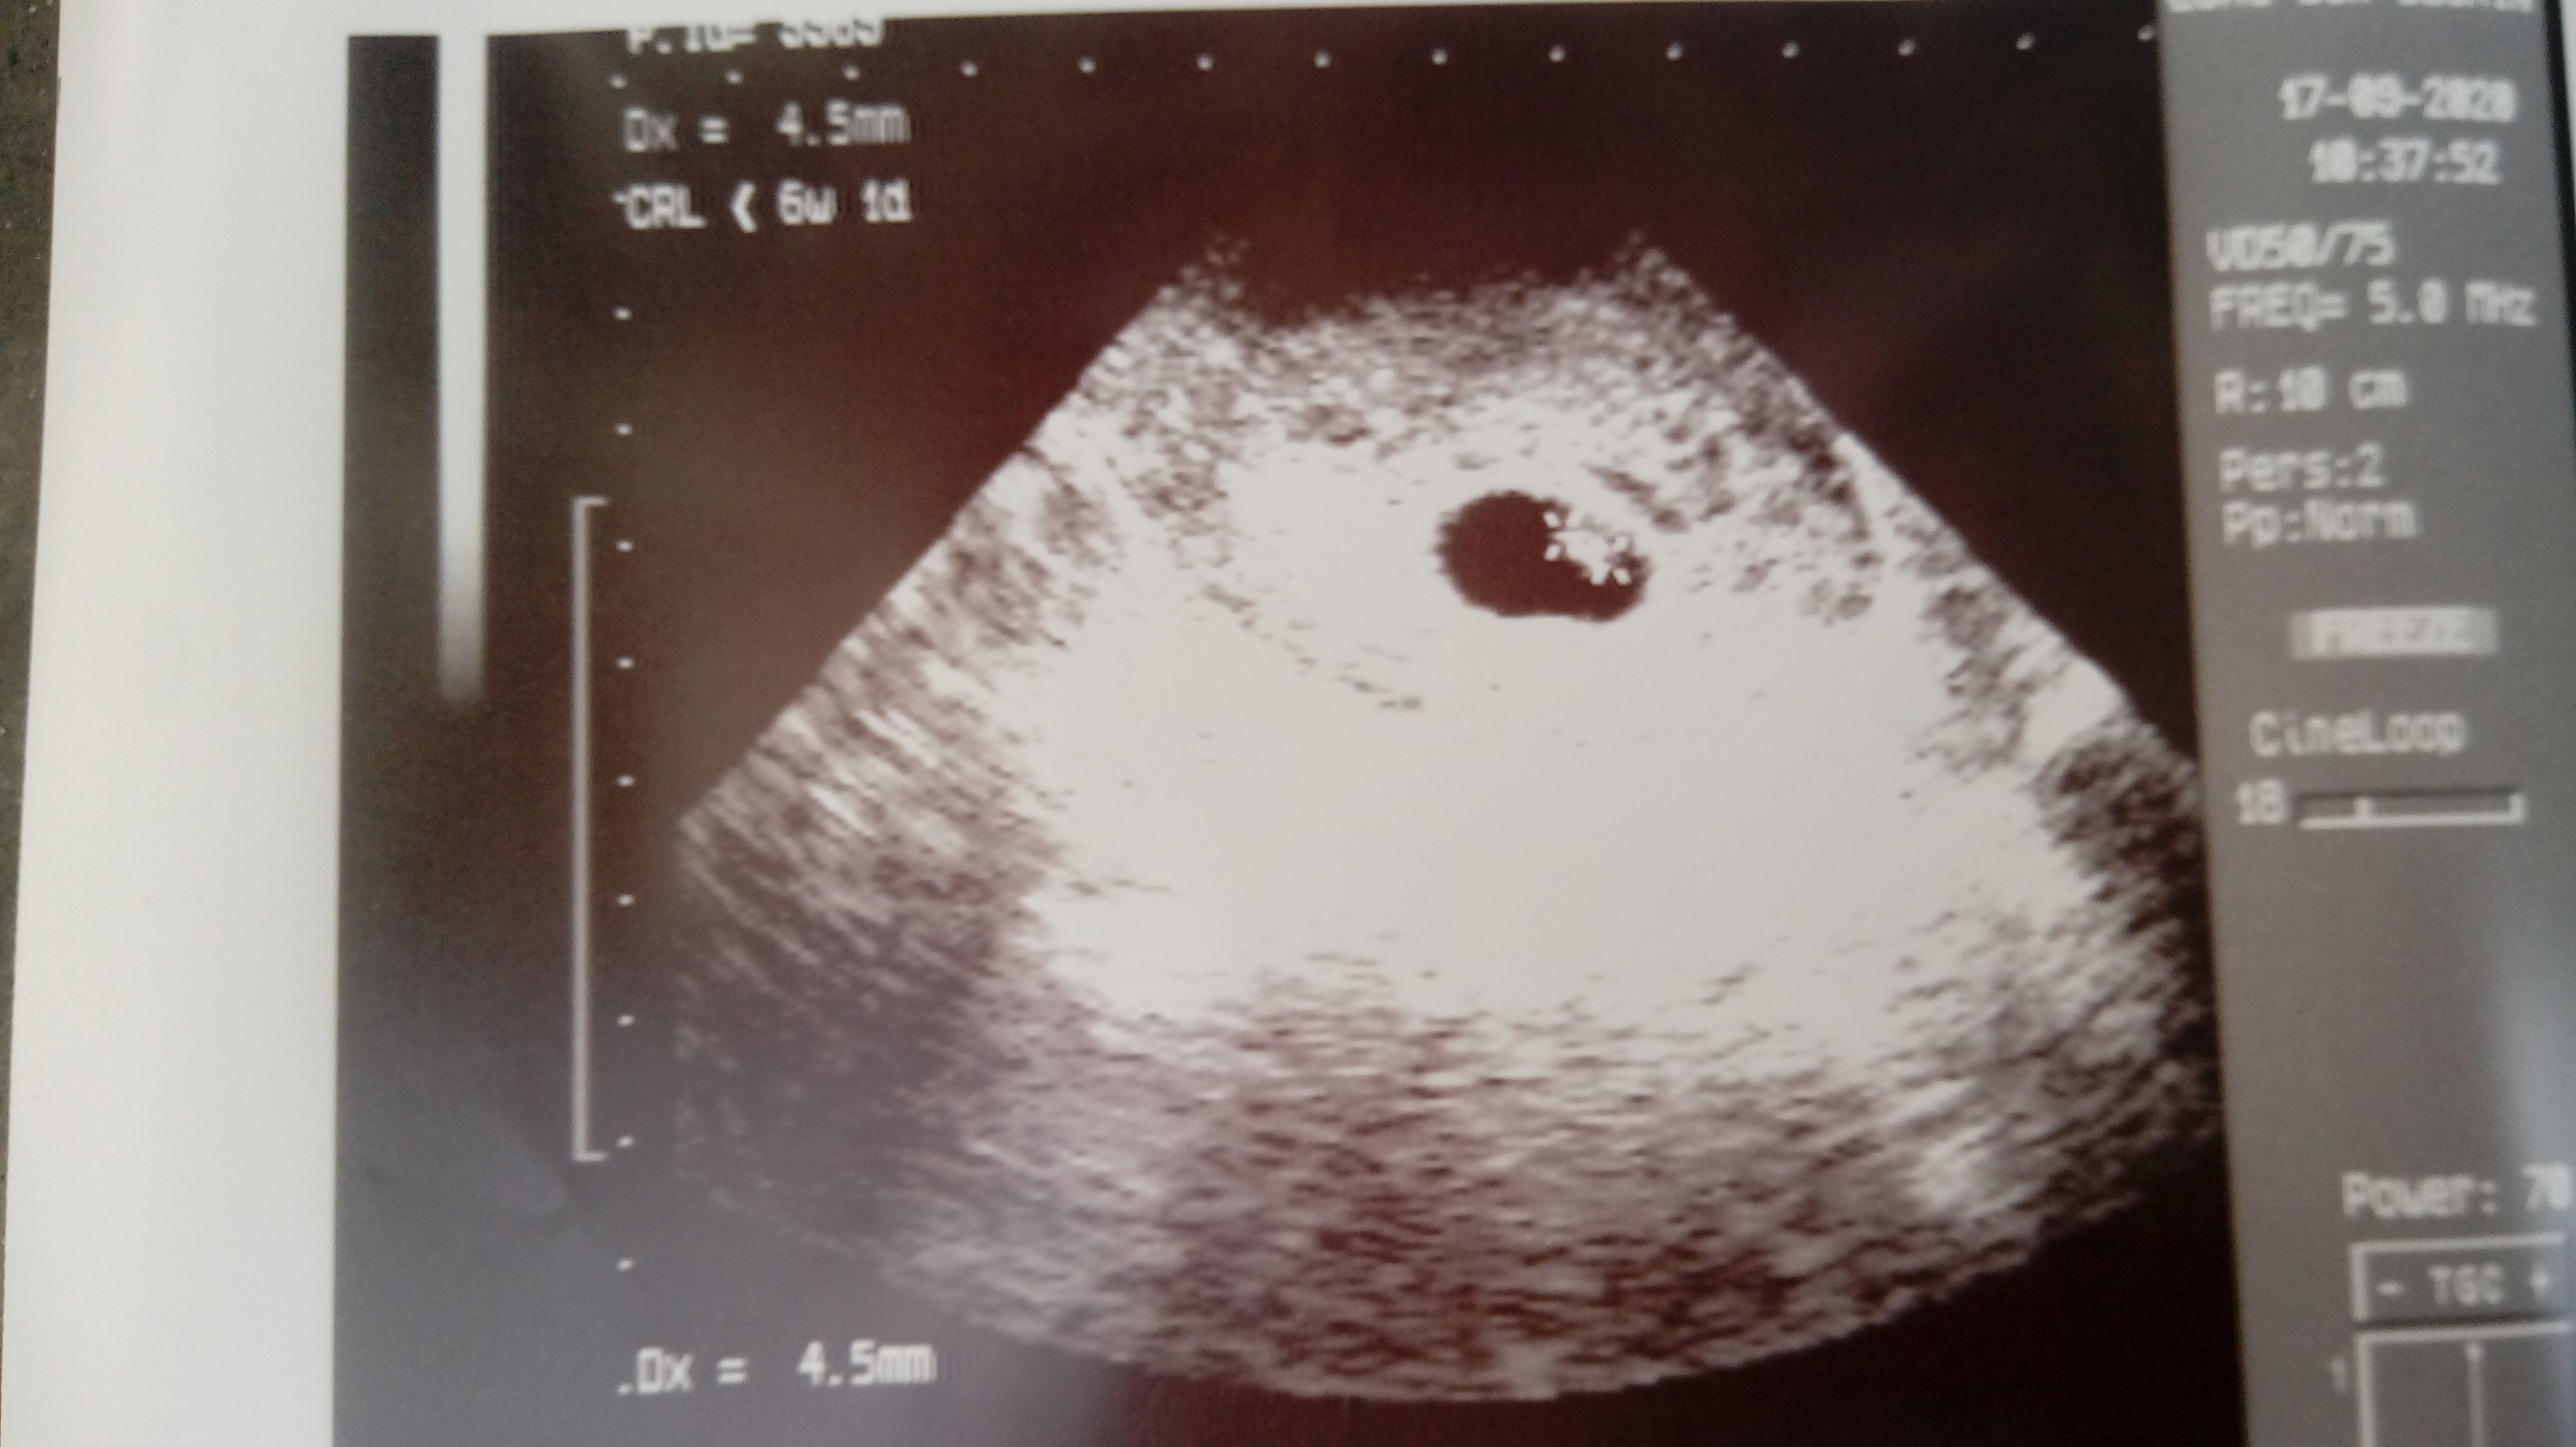

Wczoraj zaczęłam plamić co w żadnej ciąży mi się nie zdarzało. Myślałam , że przejdzie i to chwilowe bo powinnam mieć miesiączkę w tym terminie, ale dzisiaj rano jeszcze większe plamienie i skrzep krwi. Pojechałam na IP i niestety na USG nie było widać dalej zarodka, pęcherzyk o nieregularnych kształtach, puste jajo i początki poronienia. Lekarz powiedział, że albo zostaje w szpitalu i farmakologicznie oczyszczam się albo idę do domu i czekam na rozwój wydarzeń i mam iść za parę dni do lekarza na kontrolę czy wszystko się w porządku. Pojechałam do domu. Wzięłam 2 dni urlopu.